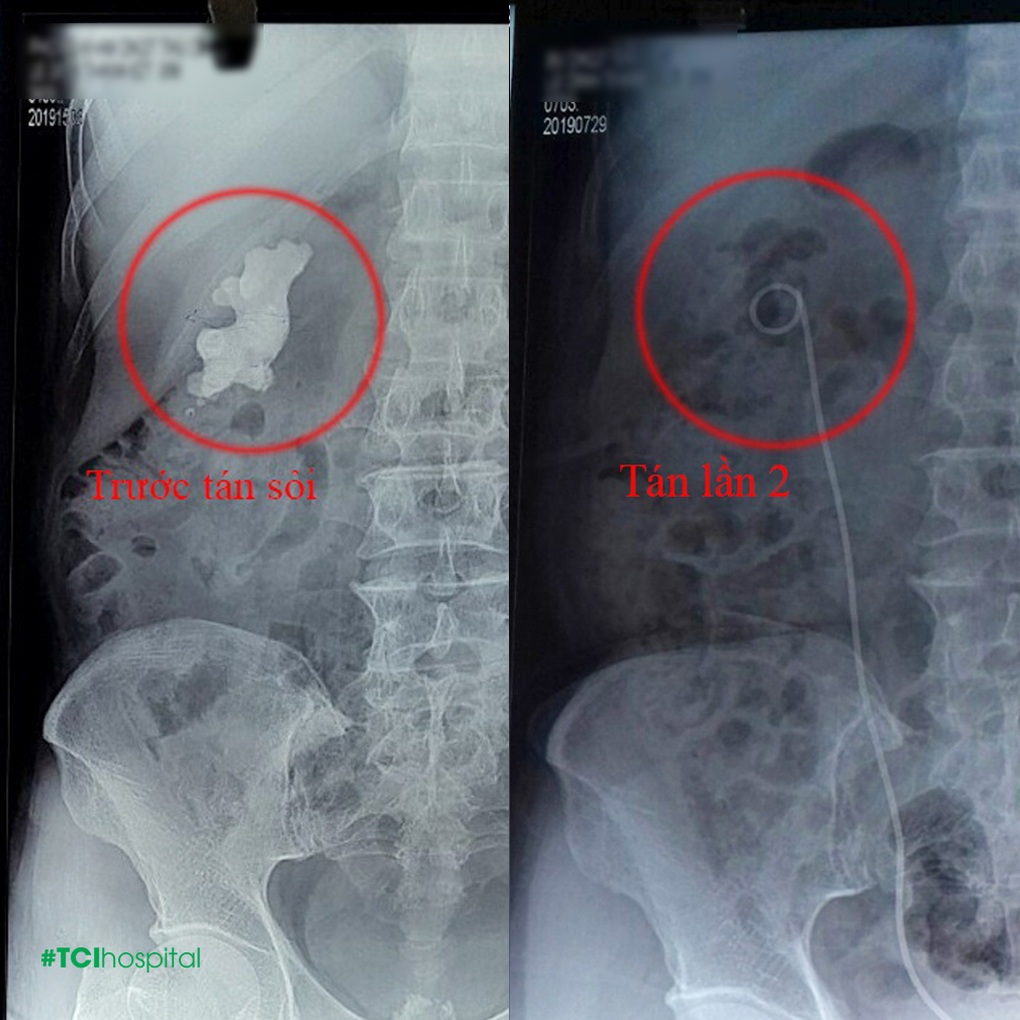

Bệnh nhân L.Đ.T. (62 tuổi) đến khám tại Thu Cúc TCI với tình trạng sỏi thận sỏi san hô kích thước tới 7cm, to như củ gừng. Bệnh nhân cho biết do có tiền sử mổ mở 2 lần lấy sỏi nên việc mở lần nữa là khá khó khăn. (Đã khám ở nhiều nơi nhưng bị từ chối do đã có tiền sử mổ mở 2 lần lấy sỏi nên việc mổ mở là khá khó khăn).

Tuy nhiên, sau khi xem xét, BSCKII Phạm Huy Huyên (Phó Chủ Tịch Hội Thận Tiết niệu miền Bắc, Phó Giám đốc kiêm Trưởng khoa Ngoại tiết niệu Bệnh viện ĐKQT Thu Cúc) cho biết có thể sử dụng phương pháp tán sỏi công nghệ cao trong trường hợp này. Bác sĩ đã quyết định sử dụng phương pháp tán sỏi qua da đường hầm nhỏ để giúp bệnh nhân loại bỏ sỏi thận an toàn bằng cách tạo một đường hầm nhỏ và thận sau đó tán vụn sỏi bằng sóng siêu âm hoặc laser. Các mảnh vụn sỏi sẽ được gắp hoặc hút ra ngoài. Nhờ phương pháp này mà bệnh nhân đã được loại bỏ sạch sỏi thận sau 2 lần thực hiện tán sỏi mà không cần mổ mở.